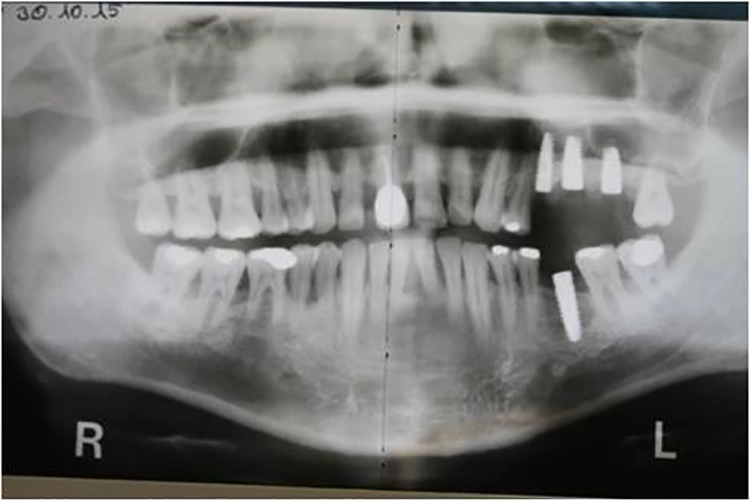

5. Multiple Sofortimplantationen in Zusammenhang mit internem Sinuslift

Beim vorliegenden 54-jährigen Patienten mussten aufgrund von lokaler Parodontitis die Zähne 25, 26 und 27 entfernt werden. Im apikalen Bereich lag jedoch gesunder Kieferknochen vor, sodass eine Sofortimplantation möglich war. Aufgrund der guten Einsichtbarkeit des Operationsgebietes nach Zahnextraktion konnte in diesem Fall flapless vorgegangen werden.

Dr. Plöger

In regio 26 konnte das Implantat dabei komplett apikal im gesunden Knochen verankert werden. In regio 27 jedoch wurde lediglich eine Restknochenhöhe von 8 mm bestimmt. In diesem Fall wurde die Sofortimplantation mit einer internen Sinusbodenelevation nach Summerset kombiniert.